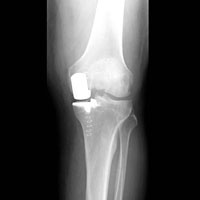

hirslanden-teil-und-miniprothesen-als-alternative-zur-knietotalprothese-2

Abb. 2

«Warum nicht nur das ersetzen, was auch kaputt ist?» Diese Frage stellt sich auch bei Eingriffen am Kniegelenk. Seit Jahren wird bei Arthrose des Kniegelenks meistens der Einbau einer Knietotalprothese empfohlen. Unabhängig vom Ausmass der Schädigung wird dabei das ganze Kniegelenk ersetzt. Gerade bei aktiven Patienten mit hohen Alltags- und Freizeitansprüchen erfüllt das Ergebnis oft die Erwartungen nicht. In der letzten Zeit haben sich Konzepte zum Einbau von Teil- oder Miniprothesen am Kniegelenk etabliert. Diese ersetzen lediglich den defekten (arthrotischen) Teil des Kniegelenks durch künstliche Materialien, der intakte Anteil des Gelenks bleibt erhalten.

Verschiedene technische Details führen dazu, dass das Knie durch den Einbau einer Teilprothese weniger belastet wird als mit einer Totalprothese. Die Gelenkreflexe und die Bänder bleiben erhalten und der minimalinvasive Zugang beim Eingriff ist gewebe- und weichteilschonend.